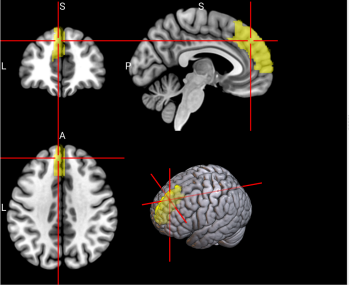

128

R Ventral Lateral nucleus of the thalamus (tAV)

The ventral lateral nucleus of the thalamus plays an important role in motor control and receiving, integrating, and projecting inputs from cerebellum, striatum, and cortex to the primary motor cortex [68].

/word/media/image17.png/word/media/image17.png